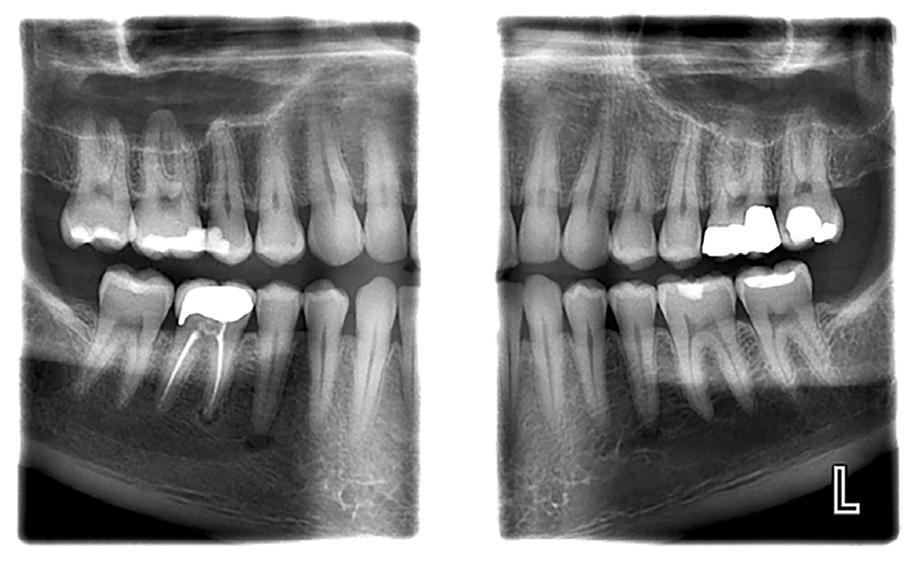

Today, approximately 40% to 50% of dental offices use digital intraoral scanning, and this percentage is only expected to grow.1 Current systems include a scanner with the head created to fit within the oral cavity to capture files of the entire dentition. The files can be used to create restorations as well as appliances either within the dental office or via a lab. While digital intraoral scanning once focused solely on restorative needs, the opportunities for its use have expanded to applications in orthodontics and pathologies such as caries, erosion, and oral cancer. In modern dental practices, this technology can also be integrated into the dental hygiene appointment.1-4

The accuracy of the digital impression comes from the scanner’s ability to capture hundreds of images per minute that are stitched together to create a complete three-dimensional (3D) view of the oral cavity.1 The sharp focus found in 3D images ensures greater accuracy for a whitening tray, restoration, prosthesis, or

appliance to fit properly. Chandran et al6 concluded that digital impressions are more likely to produce accurate impressions compared to physical impressions based on marginal fit and the fit of restorations. There is no contraction or expansion of digital impressions as can be found in physical impressions.